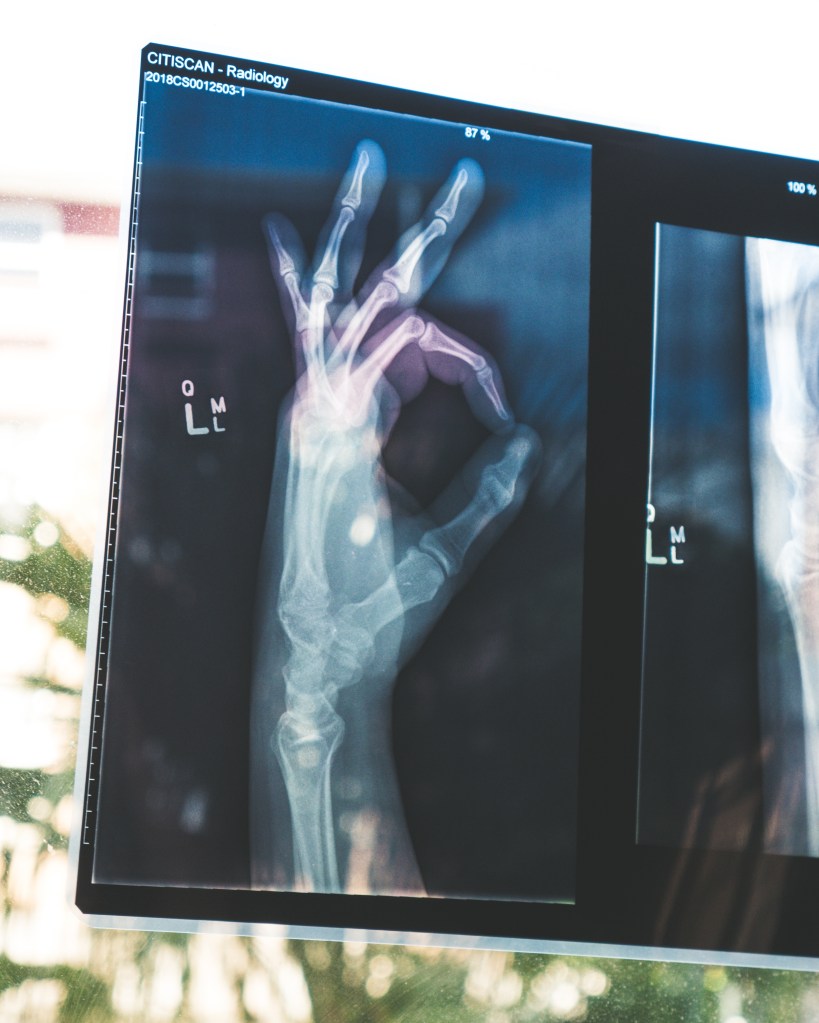

Our bones are the structural framework that supports our bodies, and maintaining their health is vital for overall well-being. From childhood through old age, bone health plays a significant role in our daily lives. In this blog post, we’ll explore the importance of bone health, how to maintain it, and why it’s a critical aspect of our overall wellness.

- Bone Composition: Bones are living tissues made up of collagen and minerals, primarily calcium and phosphorus. This unique composition gives them strength and flexibility.

- Bone Formation: Bones are constantly undergoing a process of remodeling, where old bone is broken down and new bone is formed. This process is influenced by various factors, including diet, physical activity, and hormonal changes.